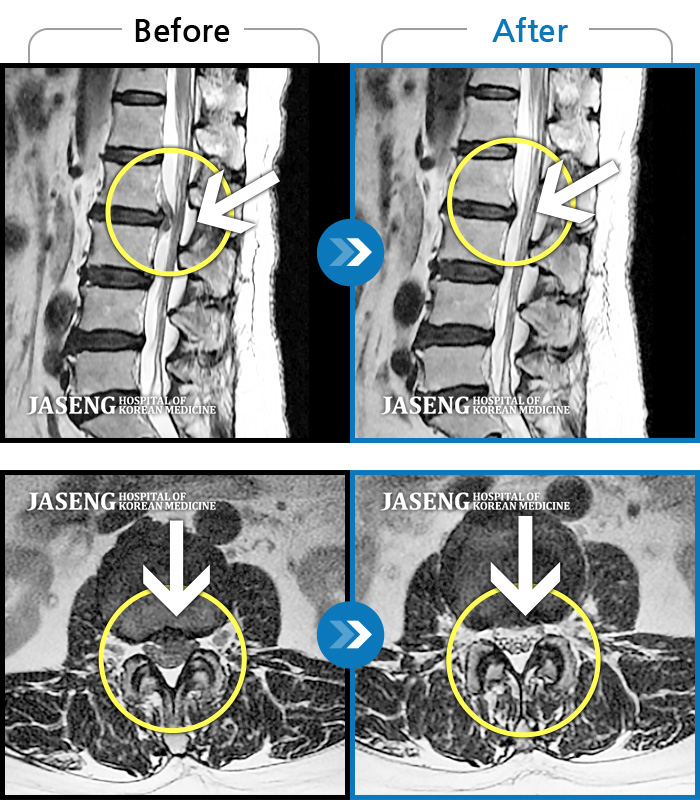

MRI 치료사례

허리디스크로 인한 허리통증